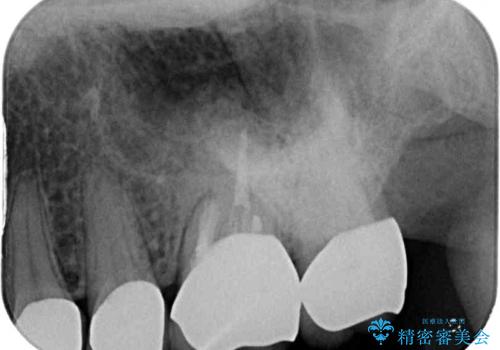

左右ともに歯根が破折しており、抜歯が必要であったため、抜歯後にインプラント補綴治療を行うこととしました。

左側は骨欠損が著しいことが予想されるため、骨造成術並びに歯肉移植術を併用することとしました。